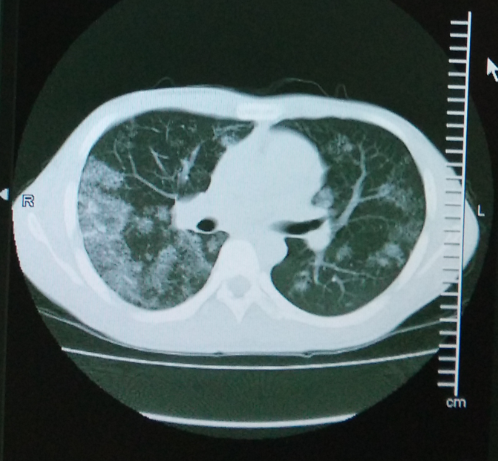

体查:T 36.8℃,BP 125/80mmHg,R 20次/分,P 80次/分。全身皮肤及粘膜未见瘀斑、黄染、苍白,全身浅表淋巴结未触及肿大。双肺活动度一致,叩诊清音,双肺呼吸音稍粗,未闻及明显干湿啰音。心腹查体无异常。生理反射存在,病理反射未引出。 辅查:尿酸UA 607umol/L ↑,红细胞沉降率(ESR,毛细管法) 25mm/h ↑;胸部增强CT:双肺多发多形性病变,以中上肺为主,右侧胸膜增厚、右侧胸腔多发包裹性积液,综合考虑为肺结核。支气管镜病理结果:右上叶后段送检直径0.2cm碎组织一堆,全埋制片。镜下:少量肺及支气管组织,其内见类上皮细胞团及多核巨细胞形成,伴小灶凝固性坏死,形态符合慢性肉芽肿性炎,考虑结核可能性大。刷片见支气管粘膜柱状上皮细胞,未见癌细胞。

随访:患者目前服用四联抗结核药,依从性较好,病情平稳,遂出院。 讨论:本病例患者无盗汗、低热、消瘦等典型结核症状,影像学结果也不是结核典型的部位和表现,单从病史及影像学依据,不能排除合并特殊病原菌感染及肺泡蛋白沉着症,所以安排患者进行支纤镜+病理活检以明确诊断。病理活检结果支持结核诊断,对患者进行四联抗结核治疗,同时嘱患者定期检查肝肾功能、血常规,定期复查胸部影像学。